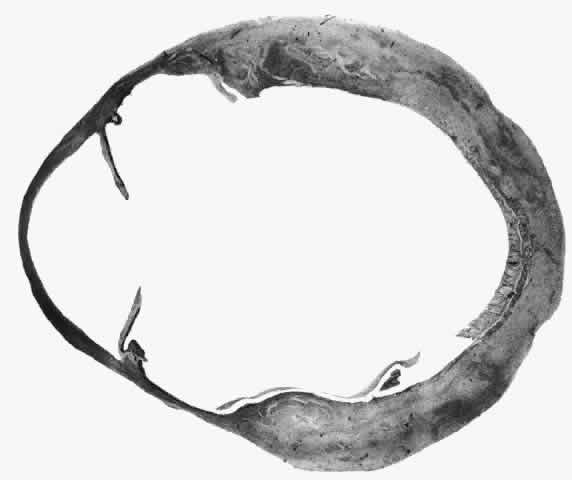

Scleritis usually affects the anterior segment of the eye, possibly because this is the area with the best blood supply, but with sluggish flow through the vessels (Fig. 19). The sclera is thickened and roughened in the affected area, which appears to be sharply demarcated from the rest of the sclera. However, tissue obtained at surgery during the course of grafting of areas adjacent to necrotic tissue shows marked pathologic changes.20,21 The area of affected sclera may be swollen, excavated, or frankly ulcerated with undermined edges covered with a thin layer of fibrous tissue. However, spontaneous perforation is extremely unusual and, where seen in pathologic specimens, has usually occurred at the time of removal of the eye. A posterior scleritis often occurs as an extension of anterior disease; but, as in Figure 20, most of the inflammation (in some cases all of the inflammation) is in the posterior segment and the exudative detachments and subretinal granulomas can be mistaken for malignant melanoma.

Fig. 19. Anterior necrotizing scleritis. The eye was removed because of loss of vision and intractable pain. No form of steroid was given to this patient because of a severe Pseudomonas infection of the chest. (Courtesy of Professor N. Ashton)